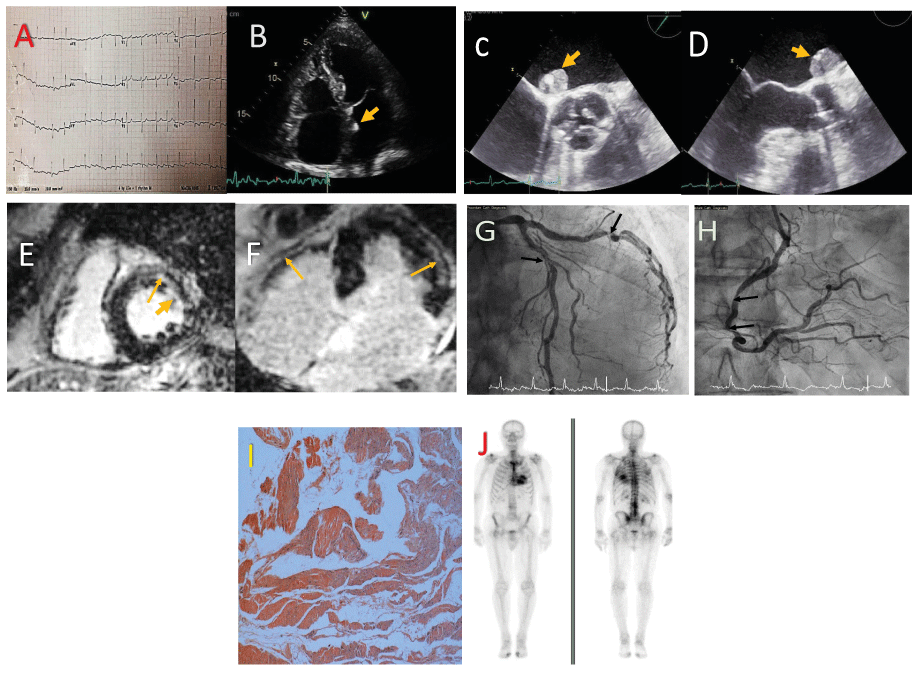

A 78-year-old man, asymptomatic with atrial fibrillation and flutter (Figure 1A) and AS, attended follow up in the valve clinic. Transthoracic echocardiogram showed a small echo- bright mass in the left atrium, along the atrial septum. (Figure 1B).

A. Twelve-lead ECG demonstrating LVH with non-specific ST and T wave abnormalities.

B. Apical4-chamber transthoracicsystolic image demonstrating bi-atrial dilatation and a small echogenic mass attached to the left side of the atrial septum (arrow).

C and D. Transoesophageal short axis image at the base of the heart and long axis image, demonstrating in greater detail the mass attached to the atrial septum (arrow).

E and F - Late gadolinium enhancement on mid-cavity short-axis and on horizontal long axis images demonstrating coarse mid-wall fibrosis of both ventricles (thin arrow) as well as subendocardial fibrosis in the LV (thick arrow).

G and H - Left and right coronary artery angiograms demonstrating diffuse atherosclerosis with areas of focal stenosis in all 3 main branches (arrows) and acceptable distal ‘targets’ for by-pass grafting.

I. Congo red stained section of myocardial biopsy highlighting abnormal protein deposits.x40 magnification.

J. DPD scan showing increased tracer uptake within themyocardium.

Transoesophageal echocardiogram demonstrated severe AS with an aortic valve area on planimetry of 0.8 cm2 with mild central aortic regurgitation, and a 1.4 cm x 1.7 cm mass attached to the left side of the interatrial septum. (Figures C and D) (Clip 1) (Clip 2).

Urgent cardiac magnetic resonance imaging showed LVEF 43%, asymmetrical left ventricular hypertrophy with a maximal wall thickness of 13 mm and severe degenerative AS with AVA 1.0 cm2 on planimetry. There was diffuse circumferential subendocardial and mid- wall LV fibrosis suggestive of amyloidosis and a sessile mass attached to the inferior rim of the fossa ovale in the left atrium, likely a myxoma (Figures E and F).

Preoperative coronary angiogram showed moderate proximal LAD disease, significant proximal LCx disease and moderate diffuse RCA disease. (Figures G and H) (Clip 3)(Clip 4).

The patient underwent an uneventful resection of the left atrial mass together with aortic valve replacement (25mm Perimount bioprosthesis) and coronary artery bypass using 3 grafts. Biopsies confirmed myocardial amyloid deposits (Figure I) and a myxoma. The patient was discharged on postoperative day 10.

Review in outpatients showed excellent recovery from surgery. There was no plasma cell dyscrasia on serum and urine electrophoresis. Technetium-99m (99mTc) and 3,3- diphosphono-1,2-propanodicarboxylic acid (DPD) scan showed early (grade 1-2) cardiac amyloid involvement (Figure J), while serum amyloid P component (SAP) scan showed no visceral amyloid deposits. TTR genetic testing was negative. The patient was doing well clinically and was started on a trial of Transthyretin stabiliser AG 10.